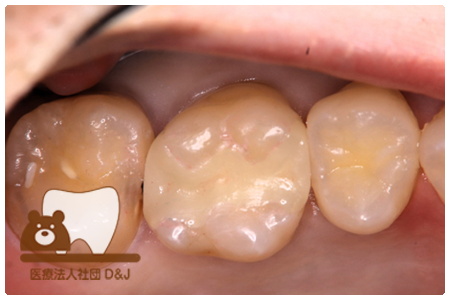

症例8フルジルコニアクラウン

治療前

治療中

治療後

29歳 女性

- 治療内容

- 銀歯からフルジルコニアクラウンへの修復

- 治療期間

- 根の治療含め3か月

- 費用

- 自費

フルジルコニアクラウン:77,000円(税込)

- その他の治療の費用は含まれておりません。

- リスク・副作用

- 強い衝撃が加わると欠けたり割れたりする可能性があります。また、噛み合わせの状態によっては脱離や周囲の歯への影響が出ることもあります。